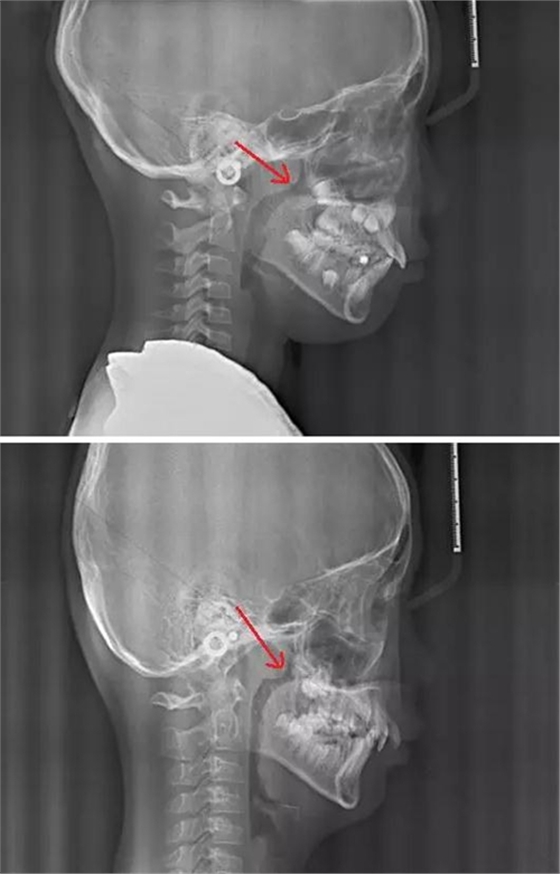

賀老師提到兒童青少年最常見的兩種阻塞呼吸道的問題即腺樣體肥大和扁桃體肥大。首先我們通過頭顱側(cè)位片來了解一下這兩個腺體在x線片上的位置。

以下兩張標(biāo)注的是肥大的腺樣體及其位置